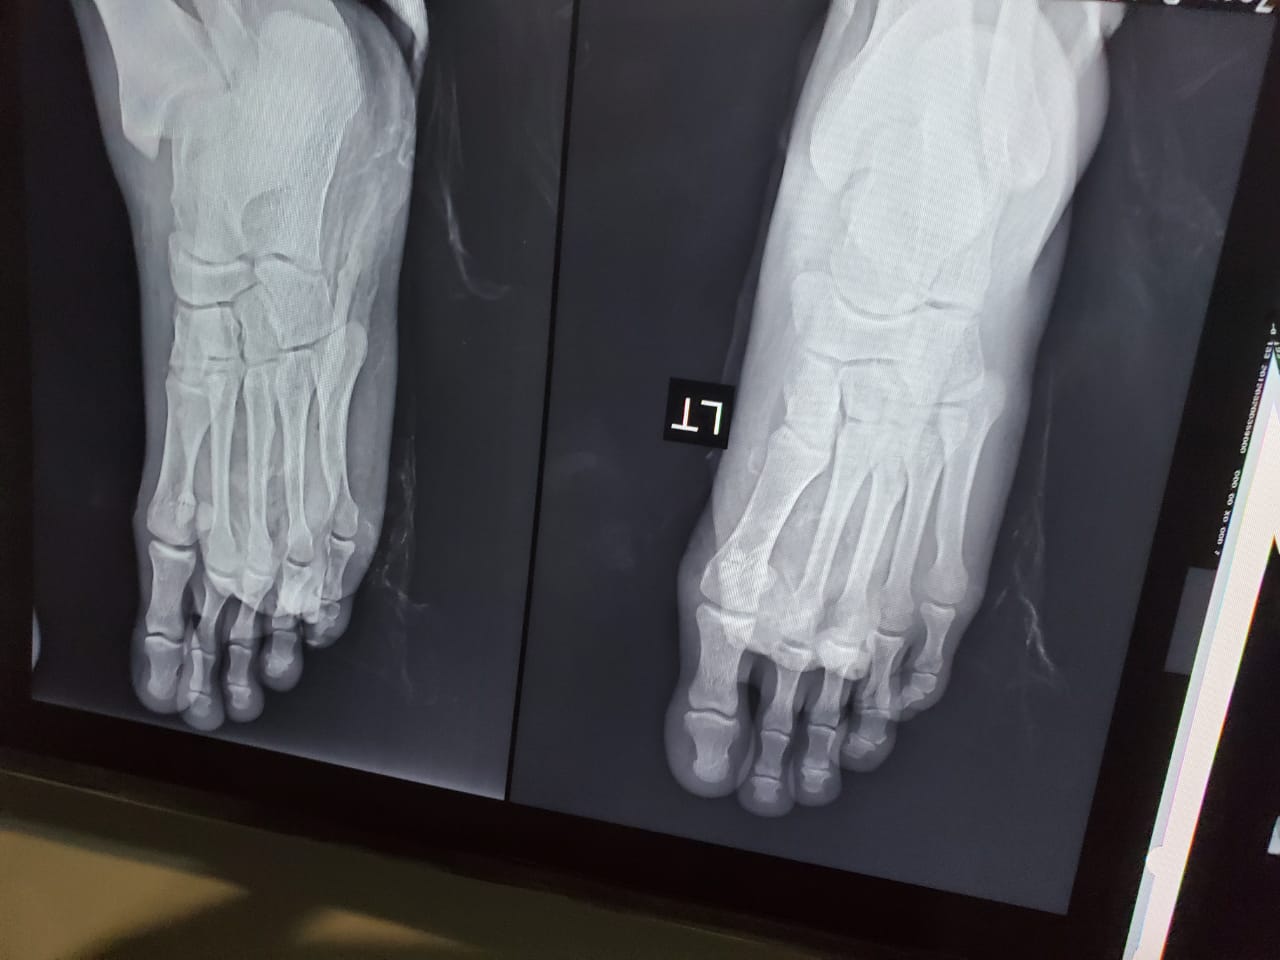

ويقول فى رسالته : انا لسه متجوز من 5 ايام فقط، وكنت رايح مشوار انا وزوجتى ، و أصبت في حادث موتوسيكل أدى إلى كسر في الساق وصعوبة في الحركة، والأطباء أشاروا بضرورة إجراء عملية وتركيب مسمارًا و شرائح، وظروفى المادية حاليا لا تسمح لى بإجرائها ، ومش قادر اتحمل الألم .